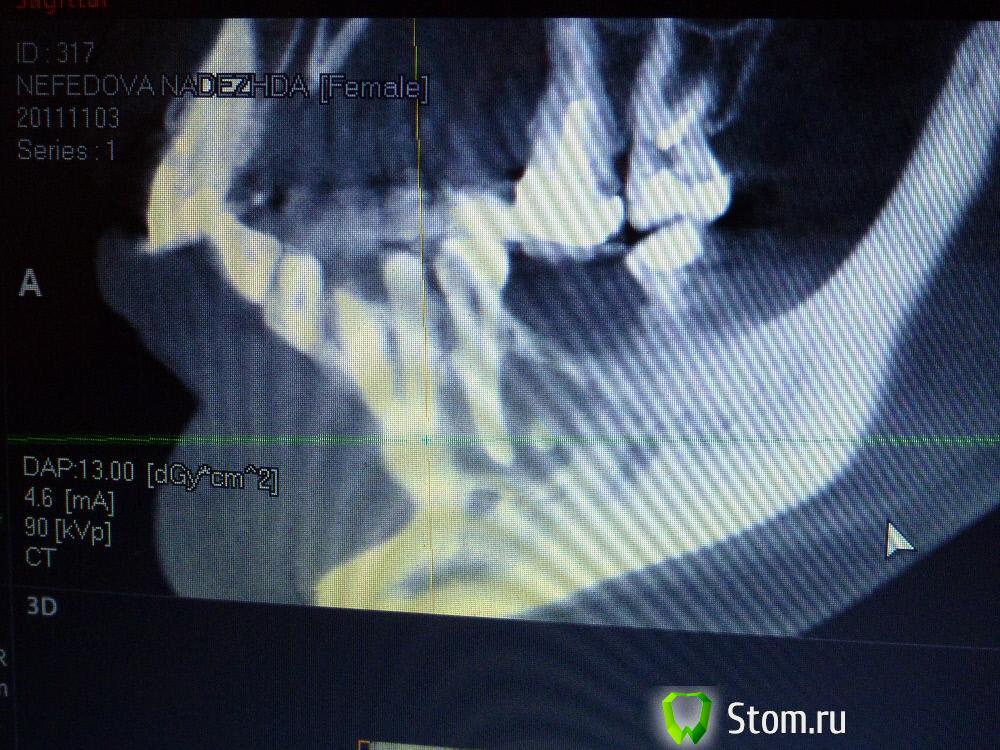

IvanK Опубликовано 25 ноября, 2011 Поделиться Опубликовано 25 ноября, 2011 Коллеги , посоветуйте Ваш план лечения.Пациентка обратилась с целью протезирования. Была направлена на ОПТГ. Обнаружены "кисты".Предположены амелобластома или первичная киста. Направлена на кафедру в 1 мед. Сказали, что "обычные кисты".Вижу 2 варианта:1). эндодонтическое лечение, цистэктомия, гистология, резекция верхушек корней, наблюдение, далее костная пластика?, имплантация. 2) Удаление зубов с периапикальными изменениями + 8-ка, гистология, пластика, имплантация боковых отделов. Ссылка на комментарий

IvanK Опубликовано 25 ноября, 2011 Автор Поделиться Опубликовано 25 ноября, 2011 Сразу прошу прощение за качество фотографий Ссылка на комментарий

koss Опубликовано 26 ноября, 2011 Поделиться Опубликовано 26 ноября, 2011 34 это полные вилы в плане эндодонтии . но попробовать было бы интересно Ссылка на комментарий

Afffinity Опубликовано 26 ноября, 2011 Поделиться Опубликовано 26 ноября, 2011 ИМХО, 38 и 45 лучше удалить Ссылка на комментарий

Corvalus Опубликовано 26 ноября, 2011 Поделиться Опубликовано 26 ноября, 2011 Эндодонтическое лечение: 45,44,33-го тоже он в зоне кисты,34,36. Хуже дела обстоят с 35-м, глянуть бы прицельный снимок, если периапикальные изменения есть, то шуруп трудно достать будет. Обязательно реэндодонтия 43. Далее цистэктомия без всяких резекций с обязательной гистологией. Заполнять кисты не стал бы, достаточно крови, очаг гнойный. Через несколько недель парадонтологическое лечение, после костная пластика с отсроченной имплантацией. И в конце рациональное протезирование одиночными коронками. При нормальном эндодонтическом лечении рецедива кист не должно быть, а если и будет, то не на всех зубах сразу. Себе зубы удалять не стал бы, опыт лечения таких зубов есть, с имплантацией всегда решить можно по ходу поступления проблем. Второй вариант имеет место быть. Объяснить пациентке все за и против, пусть сама выбирает. Ссылка на комментарий